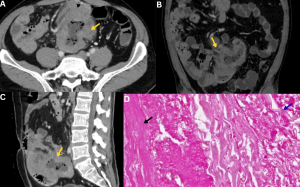

Fig 19: Clinical history:

A 58-year-old immunocompromised male presented with fever, retrosternal chest pain, and progressive dysphagia.

Figure A:

Axial CT chest image demonstrates multiple ill-defined hypodense lesions within the mediastinum (red arrow).

Figures B & C:

Axial and coronal post-contrast CT chest images demonstrate peripheral rim enhancement with central nonenhancing areas (yellow arrows), consistent with mediastinal abscesses. No definite air–fluid levels are identified.

Figure D:

CT-guided aspiration, followed by a KOH mount, demonstrates broad, aseptate hyphae, confirming mucormycosis.